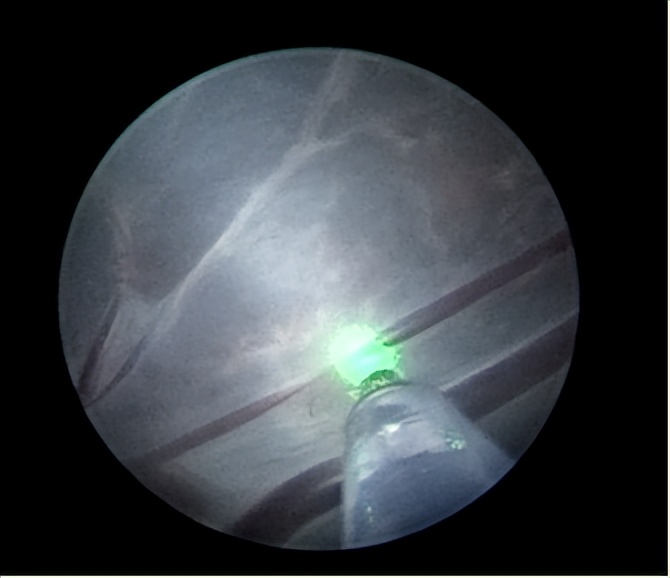

经过充分沟通与讨论,郑女士决定进行胎儿镜手术治疗。医院积极进行术前准备,超声定位确定穿刺路径。手术当天,手术团队成功完成胎儿镜下胎盘交通血管激光凝固术,手术过程顺利。

据悉,双胎输血综合征是双羊膜囊单绒毛膜单卵双胎的严重并发症。通过胎盘间的动-静脉吻合支,血液从动脉向静脉单向分流,使一个胎儿成为供血儿,另一个胎儿成为受血儿,造成供血儿贫血,血容量减少,致使生长受限,肾灌注不足,羊水过少,甚至营养不良而死亡;受血儿血容量增加,动脉压增高,各器官体积增大,胎儿体重增加,可发生充血型心力衰竭,胎儿水肿,羊水过多。胎儿镜手术可通过直径仅2mm的内窥镜,伸入孕妈妈子宫、羊水内,清楚找到双胎间隔膜以及隔膜两旁的动静脉吻合血管,激光电凝血管达到治疗目的。

胎儿镜下胎盘交通血管激光凝固术